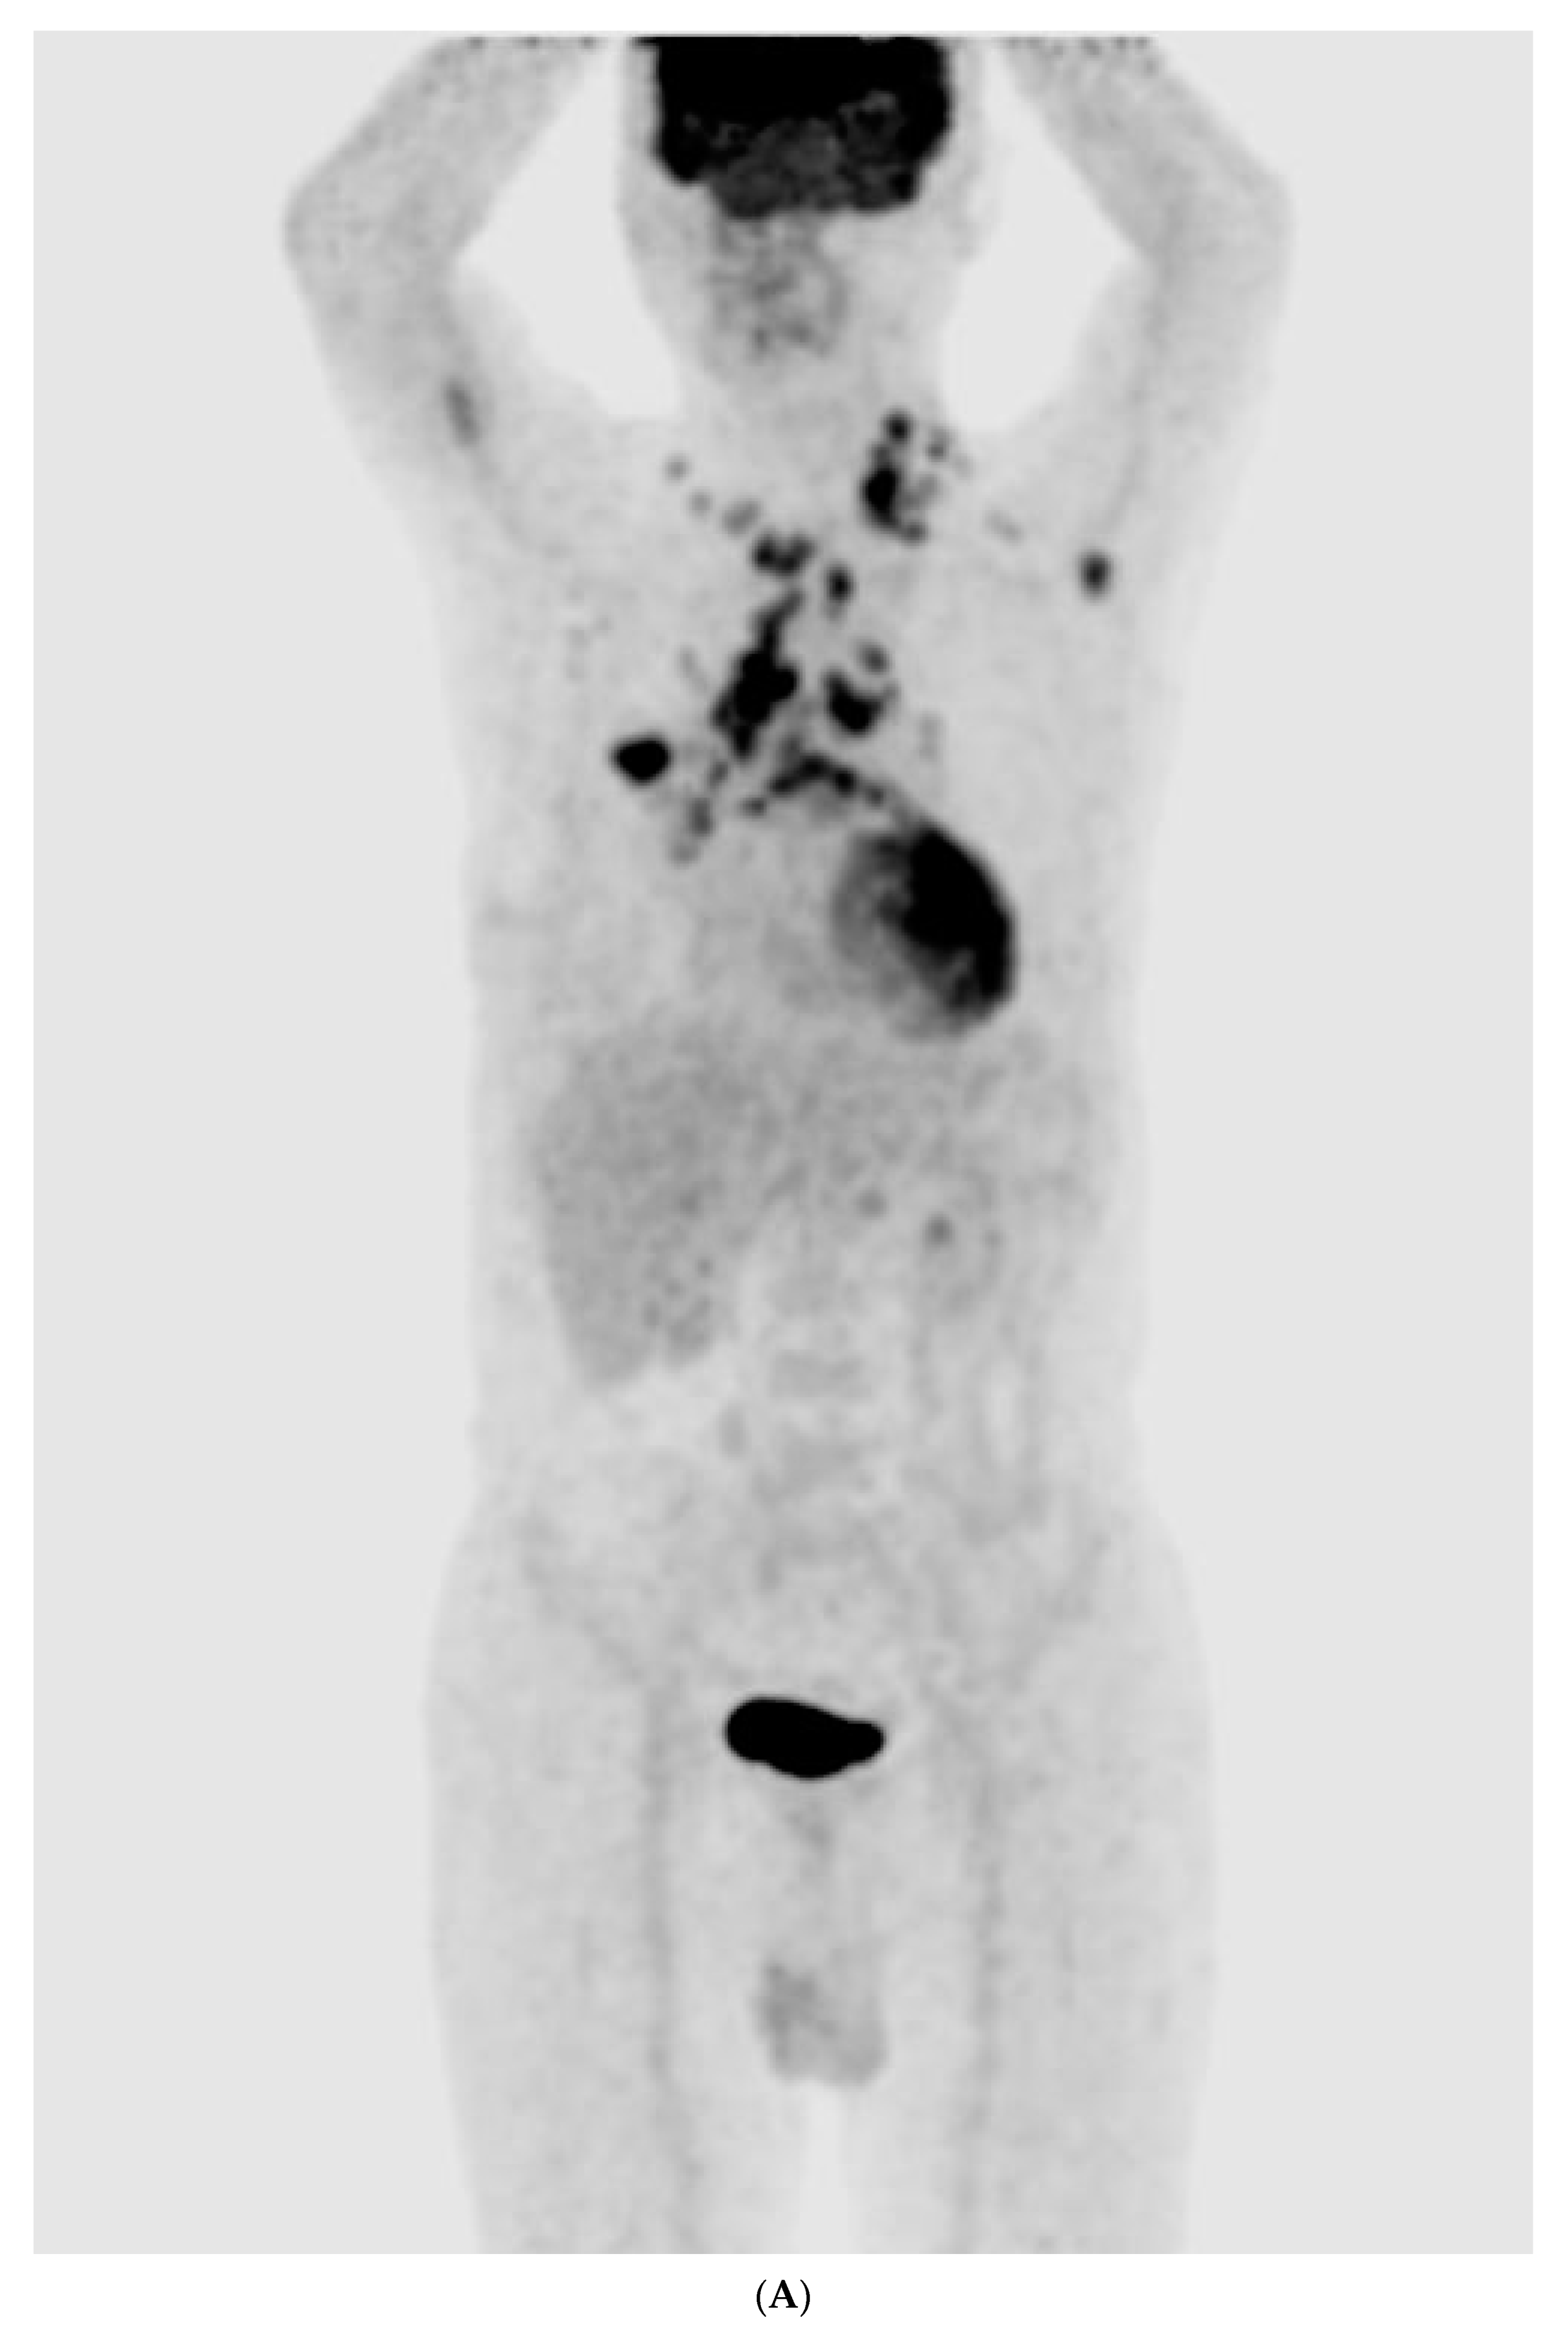

The chest radiography showed a massive right-sided pleural effusion (Figure 1A). Percutaneous catheter drainage was performed for the right-sided pleural effusion. The chest computed tomography showed a 3.3 cm × 3.0 cm mass in the right upper lobe (Figure 1B). The positron emission tomography/computed tomography revealed metastases in the left-sided supraclavicular lymph nodes, multiple bilateral mediastinal lymph nodes, and left scapula (Figure 2). The magnetic resonance imaging of the brain revealed multiple tiny cerebral and right cerebellar metastases (Figure 3). A percutaneous needle biopsy confirmed the diagnosis of lung adenocarcinoma (pT2aN3M1c, stage IVB); the analysis of the right-sided pleural effusion revealed metastatic adenocarcinoma. The genetic analysis revealed an exon 19 deletion in the EGFR gene. The laboratory tests, including the blood cell counts and chemistry, were within the normal ranges prior to treatment initiation. The patient was administered the EGFR-TKI afatinib (40 mg/day) as a first-line chemotherapy.

Figure 2.

(A–E) Positron emission tomography/computed tomography revealed metastases to multiple lymph nodes, includingleft supraclavicular lymph node, bilateral mediastinal areas, and left scapula.